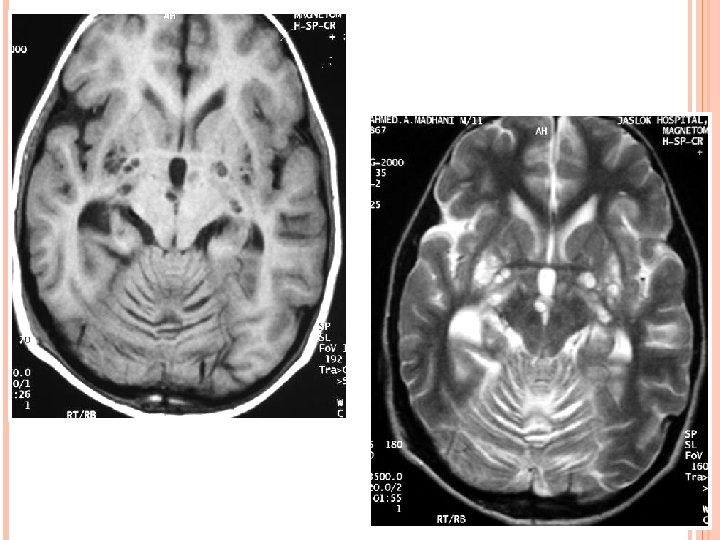

HIV ENCEPHALITIS NECT- Normal or atrophy +/- WM hypodensity. MR • • • v Volume loss with prominent sulci and ventricle. T 2/FLAIR hazy symmetric WM hyperintensity, spare the subcortical U fibers. No mass effect. Usually no enhancement and no restricted diffusion. T 1 images reveal no hypointensity. Reduced grey matter volume in superior and medial frontal gyri – possible early imaging marker. D/D- PML, CMV enchephalitis, ventriculitis; toxoplasmosis; Herpes and HHV-6 encephalitis.